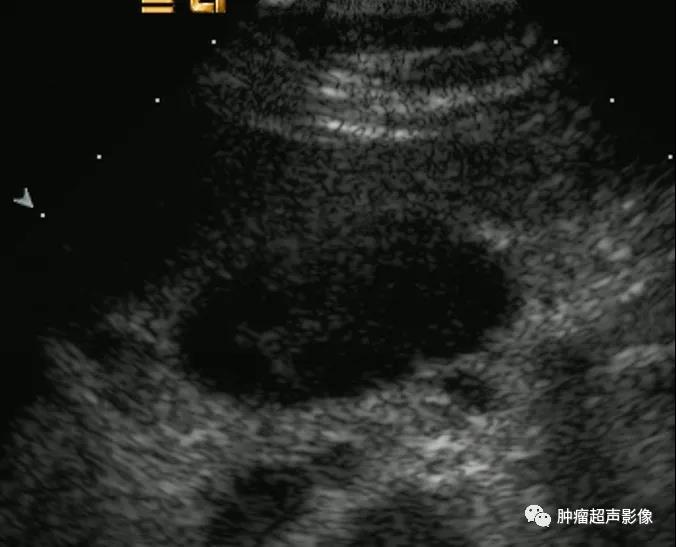

左图:胃淋巴瘤转移淋巴结,右图:胃癌转移淋巴结

胃淋巴瘤转移的淋巴结相对来说单个更大、回声更低、血流更丰富。

超声造影:左图胃淋巴瘤呈均匀高增强,

右图印戒细胞癌呈“栅栏样”非均匀增强